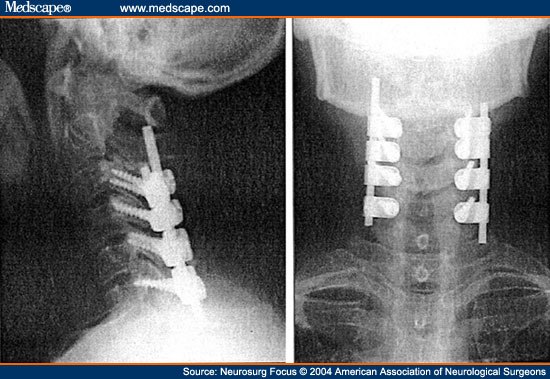

四肢肌力减退,拟行颈椎后路侧块钉棒内固定术

颈椎侧块及侧块螺钉技术

颈椎后路减压侧块钢板内固定治疗脊髓型颈椎病 - 好大夫在线

3年前在外院行颈椎椎板切除侧块螺钉内固定术,术后症状症状稍改善,现